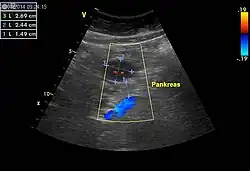

Einen wesentlichen Beitrag zur Tumordiagnose und Bestimmung der Tumorausbreitung liefern bildgebende Verfahren wie Sonografie, konventionelle Röntgenaufnahmen nach Verabreichung von Kontrastmitteln, die Computertomografie sowie die Magnetresonanztomografie. Die Positronenemissionstomografie (PET) unter Verwendung von 18F-2-Fluor-2-deoxy-D-glucose eignet sich speziell zur Erfassung von Metastasen.[3]